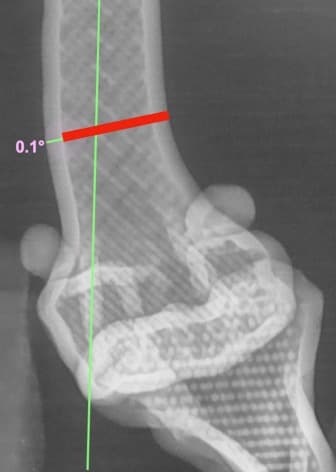

정형외과 전공의 수의사가 직접 수술합니다.

02C-arm을 통해서 좀 더 섬세한 정형외과 수술을 진행하고, 본원에서는 외과적 침습을 최소화 하는 중재적 시술 (기관 협착, 동맥관개존증(PDA), SUB 등)을 진행하고 있습니다.

13수술 중 골절 상태 혹은 이식물 적용 후 상태 등 육안으로 명확히 확인하기 힘든 상태를 X-ray 확인하여 정확한 수술 결과를 만들어 내는 것이 가능